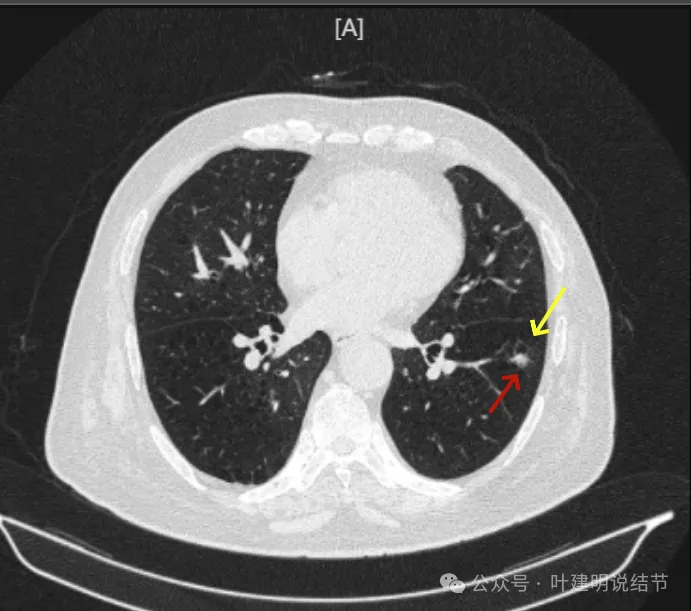

再看2024年9月时的影像:

病灶出现,紧贴叶间裂,有小血管走向病灶侧。

中间有空腔,叶裂侧实性并牵拉叶间裂。

囊腔灶、轮廓清、小血管进入囊壁、囊壁厚薄不均、叶间胸膜牵拉。

表面不平、混合密度、囊腔壁厚薄不均、内壁不光滑、有细支气管扩张通气征。

明显壁厚薄不均的囊腔灶,囊壁基本实性,表面不平,内壁不光滑,且邻近叶间裂并牵拉叶裂。

表面毛糙不平,部分区域有点像锯齿状。

表面不平细毛刺,中间空腔欠光滑、囊壁厚薄不均。

上图囊壁较厚,密度较高,轮廓与边界较清。

病灶边上也有多发小空泡样征,说明病灶有收缩力或对周围结构有影响。

上图显得像混合密度伴偏心空腔征。